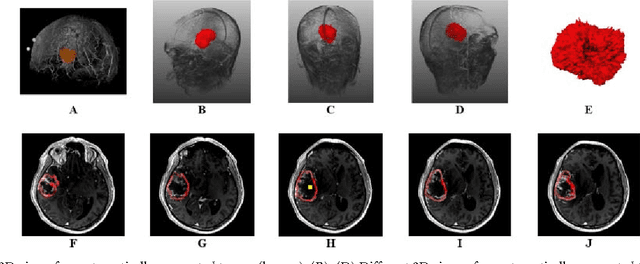

We present a scale-invariant, template-based segmentation paradigm that sets up a graph and performs a graph cut to separate an object from the background. Typically graph-based schemes distribute the nodes of the graph uniformly and equidistantly on the image, and use a regularizer to bias the cut towards a particular shape. The strategy of uniform and equidistant nodes does not allow the cut to prefer more complex structures, especially when areas of the object are indistinguishable from the background. We propose a solution by introducing the concept of a "template shape" of the target object in which the nodes are sampled non-uniformly and non-equidistantly on the image. We evaluate it on 2D-images where the object's textures and backgrounds are similar, and large areas of the object have the same gray level appearance as the background. We also evaluate it in 3D on 60 brain tumor datasets for neurosurgical planning purposes.